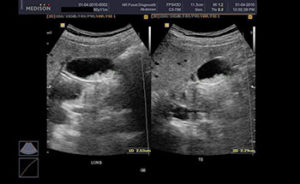

Ультразвуковое исследование показывает такой вид заболевания.

Маленькие полипы часто можно обнаружить только с помощью УЗИ, так как они не проявляются никакими симптомами.

Врачи, которые участвуют в лечении полипов желчного пузыря, включают в себя терапевта, хирурга и гастроэнтеролога. Лечение этого заболевания необходимо начинать как можно скорее, поскольку полипы могут превратиться в рак. Выбор методов лечения и назначение лекарств зависят от таких факторов, как размер полипа, симптомы и скорость его роста (быстрое увеличение размеров на 0,2 мм в течение 12 месяцев). При УЗИ полипы желчного пузыря могут быть похожи на желчные камни, однако последние всегда имеют повышенную эхогенность. Лечение полипов может включать консервативную терапию, диету, операцию или использование народных средств.